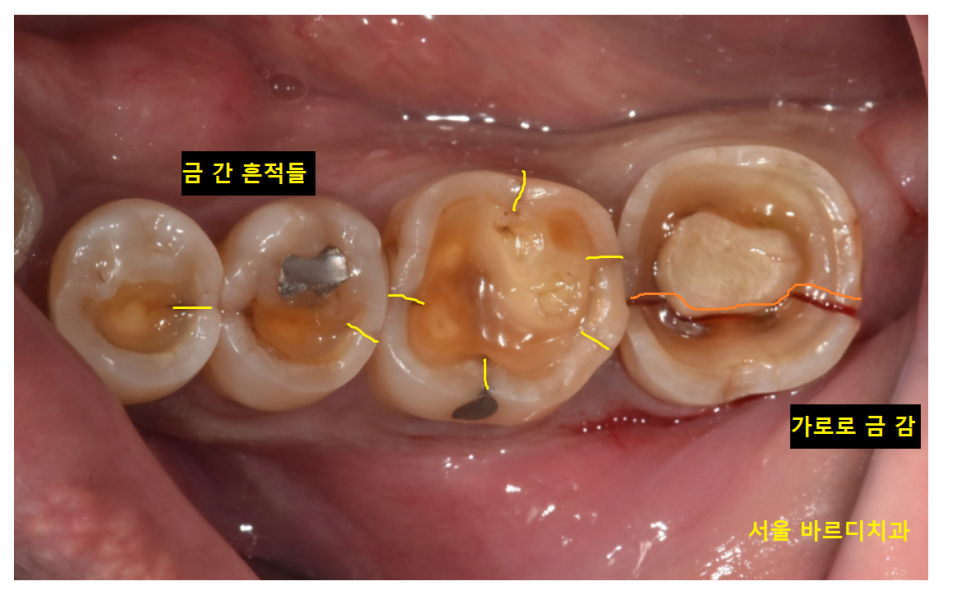

23.10.16

육안으로 보기에도 금이 보이죠~

미세한 실금은 저도 있습니다.

조심히 사용하고 증상이 없으면

딱히 치료를 안해도 되지만

환자분처럼 치아가 분리될 정도로

금이가면 뽑고 임플란트를 해주어야해요.

어금니 금감 발치 후

풍산동 임플란트 진행했습니다.